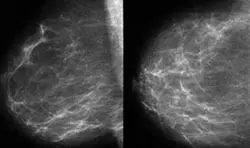

Dijital mamografi nedir ?

Digital mamografinin avantajları var mıdır?

Mamografi tüm meme kanserlerini yakalıyor mu?